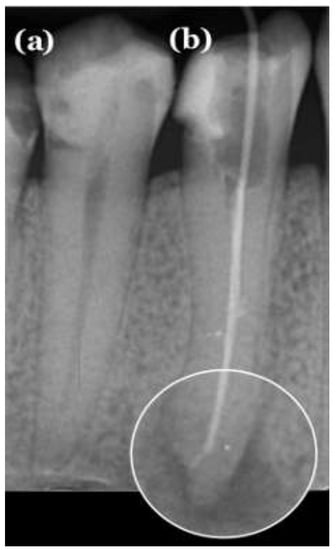

- Twelve true positives (TP) (teeth with apical periodontitis, unhealthy);

- One false positive (FP) (tooth with no signs of apical periodontitis was classified as unhealthy, over-diagnosed by the tool);

- Forty-six true negatives (TN) (healthy teeth, no signs of any apical periodontitis);

- One false negative (FN) (misdiagnosed by the tool; a tooth with apical periodontitis was classified as a healthy tooth).